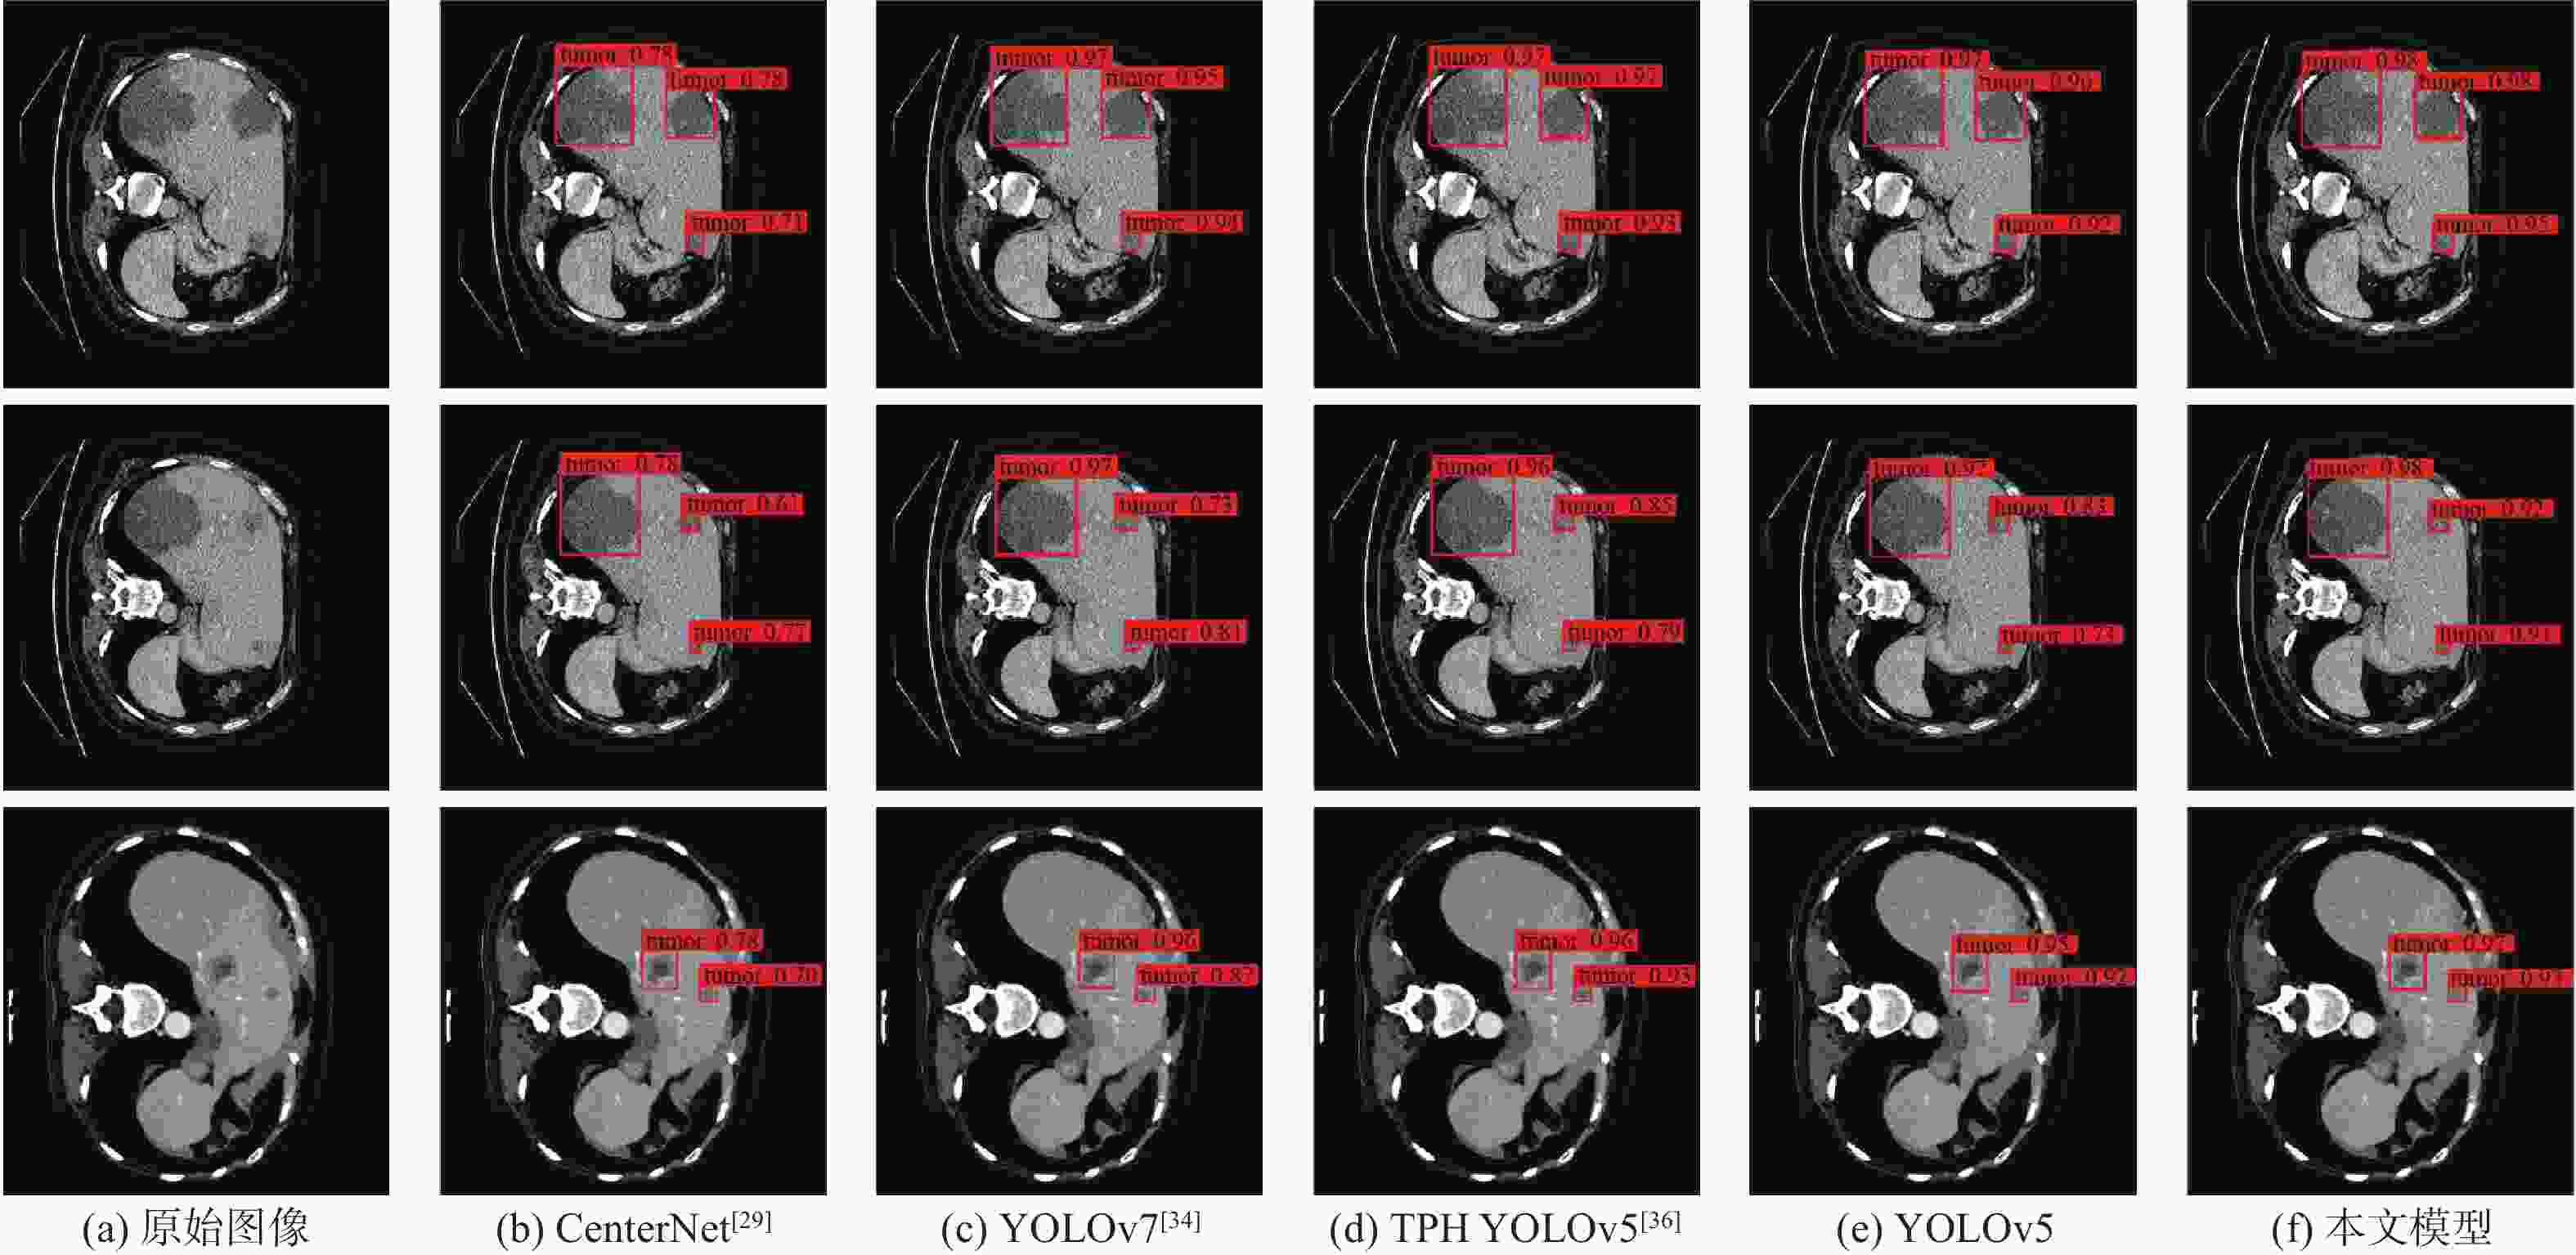

针对肝脏肿瘤检测中多尺度特征表达能力不足的问题,提出一种融合重参数化卷积、加权双向特征金字塔和注意力机制的肝脏肿瘤CT图像检测方法。使用数据增强改善样本量较少的问题,提高模型的泛化能力;使用加权双向特征金字塔网络融合图像的浅层与深层特征,提高多尺度特征的提取能力;在特征融合中引入无参数平均注意力模块,关注肝脏肿瘤的关键特征;使用重参数化卷积和边界框(SIoU)损失函数提高肿瘤的检测和定位能力。实验结果表明:所提方法在LT3DM和LiTS2017数据集上的平均精度均值(mAP)分别达到了92.9%和92.2%,比YOLOv5模型提高了2.3%和1.8%,相较于主流检测模型,所提方法具有更好的肝脏肿瘤检测能力。

Abstract:To address the problem of insufficient multi-scale feature representation in liver tumor detection, we propose a liver tumor CT image detection method that integrates reparameterized convolution, weighted bidirectional feature pyramid, and attention mechanism. Firstly, data augmentation is used to improve the problem of small sample size and enhance the generalization ability of the model. Secondly, to enhance the ability to extract multi-scale features, the weighted bidirectional feature pyramid network is utilized to merge the image's shallow and deep features. Then, a parameter-free attention mechanism is introduced in feature fusion to focus on the key features of liver tumors. Finally, reparameterized convolution and shapeaware intersection over union (SIoU) loss functions are used to improve tumor detection and localization accuracy. The mean average precision(mAP)of this method on LT3DM and LiTS2017 datasets reached 92.9% and 92.2%, respectively, which is 2.3% and 1.8% higher than that of the YOLOv5 model. The experimental results indicate that this method has a greater ability to detect liver tumors than standard detection models.

模型 P/% R/% F1/% mAP/% 参数量 浮点运

算速度/

109 s−1SSD512(VGG) [27] 93.1 62.5 74.7 84.3 23.75×106 87.55 YOLOv3[28] 88.7 73.9 80.6 82.9 61.52×106 49.68 CenterNet[29] 92.8 82.5 87.3 88.6 32.66×106 35.09 EfficientDet[30] 62.5 63.9 63.2 63.5 3.83×106 2.37 YOLOv4[32] 82.4 55.2 68.0 67.6 63.94×106 45.41 Faster R-CNN(Res50) [31] 39.4 71.8 50.9 62.2 28.28×106 241.71 YOLOX[33] 91.5 85.8 88.5 89.9 8.94×106 8.56 YOLOv7[34] 92.8 82.2 87.2 89.6 6.22×106 33.01 YOLOv5 93.6 85.7 89.4 90.6 7.02×106 15.90 PP PicoDet[35] 86.1 71.2 77.9 80.5 1.18×106 4.59 TPH YOLOv5[36] 94.2 86.9 90.4 90.9 40.82×106 36.26 YOLOv8 80.1 93.3 87.0 88.1 11.13×106 9.10 FCOS[37] 91.9 80.1 85.6 88.1 32.11×106 51.56 DETR[38] 59.8 81.3 68.9 71.7 36.74×106 23.81 MAEfficientDet-D0[7] 86.2 84.1 80.9 85.6 4.34×106 2.83 MAEfficientDet-D1[7] 86.8 84.8 85.1 86.5 7.08×106 6.81 本文模型 94.6 88.3 91.3 92.9 7.17×106 16.30 表 7 不同模型在LiTS2017上的检测性能对比